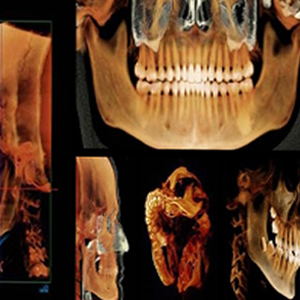

3D CT 촬영으로 치아와 치조골의 상태 및

잇몸뼈의 양과 길이 등의 상태를 정확하게

측정하여 세밀한 진단과 시술 전 발생가능한

문제점을 사전에 발견하고 대비하여

진료의 안정성을 높힙니다.

치과진료는 굉장히 세밀한 치료이기 때문에 정밀한 3D 디지털 기술을 접목하면

의료진의 판단에만 의존하던 치료를 더욱 정확하게 예측하고 진하여 오차를 줄일 수 있습니다.